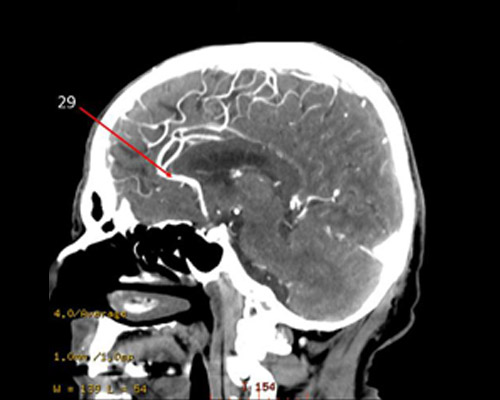

29?

anterior CA